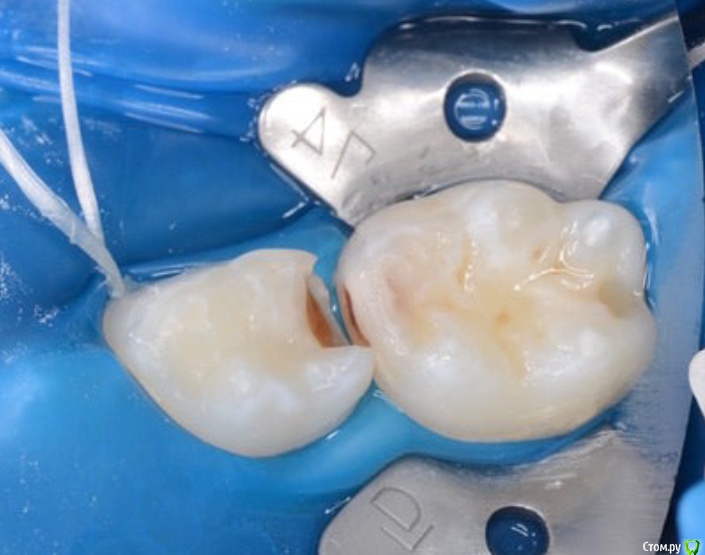

CRAZYDUCK Опубликовано 3 мая, 2018 Поделиться Опубликовано 3 мая, 2018 Обратимый пульпит 4.6 ,почти 8 лет ( в середине мая )сначала сделала силиконовый ключ .1.препарирование 2.вскрытый рог - кровотечение незначительное 3.спонтанный гемостаз (через 4-5 минут после вскрытия )4. ХГ 2% 5. МТА ( рутдент быстротвердеющий технодент ) застывает за 8-10 минут 6. Calcimol изолирующая, убираю излишки , Rondoflex 7. Реставрация с помощью силиконового ключа.8. Полировка .Наблюдаем - осмотр реставрации , витальность и RVG каждые 3-4 месяца. 6 Ссылка на комментарий